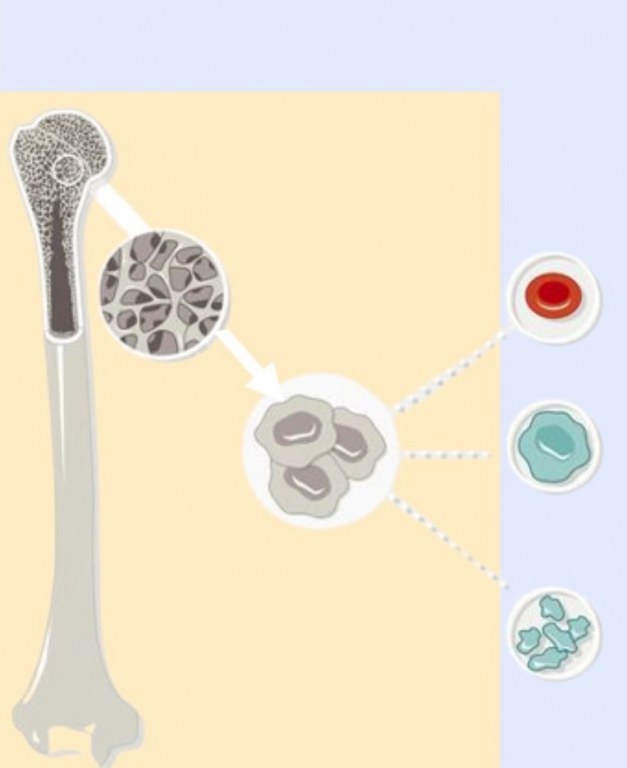

Maximizing the Potential of Primary Mesenchymal Stromal Cells

Introduction